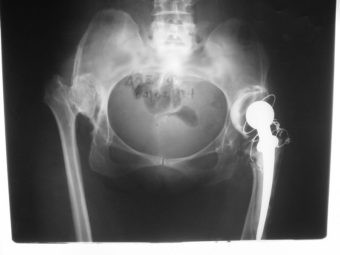

Revisión de prótesis con injerto óseo masivo

Envíado por Dr. Ricardo Antonio Gómez G.